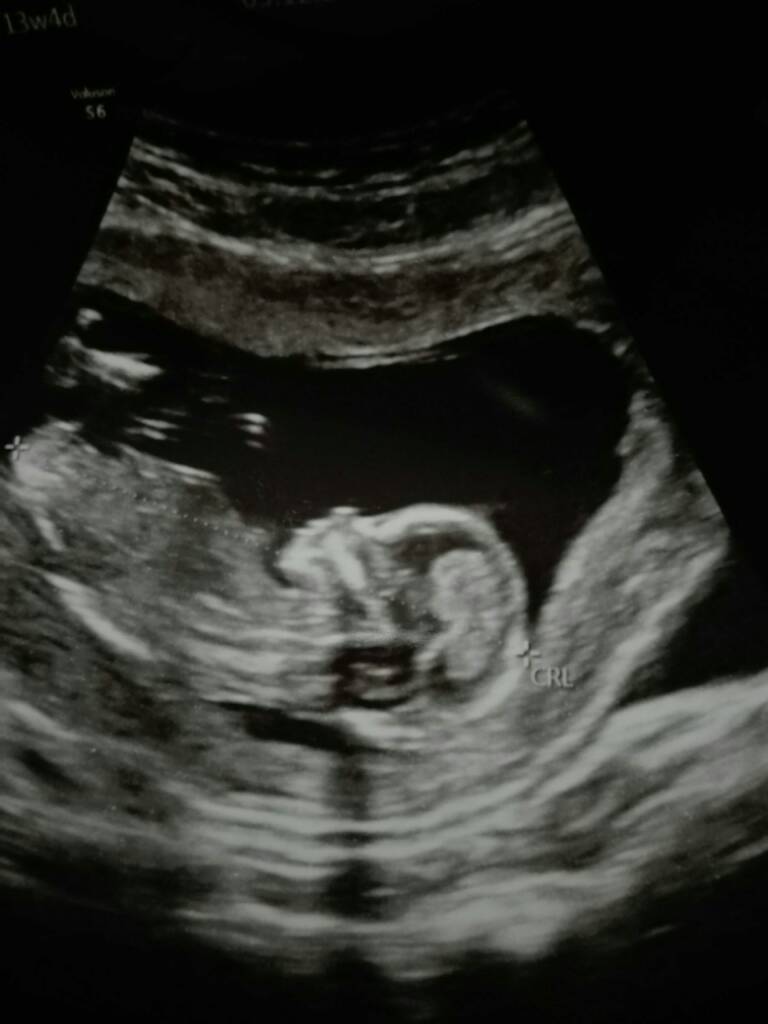

My juz po wizycie i według pani doktor z cala jej pewnoscia czekamy na dziewczynke [emoji7][emoji7]

Maluszek juz ma 7,41 cm a dzis 13+4.

Doktor długo robila mi dzis usg bo dzidza taka ruchliwa ze co probowala ją zlapac to uciekala [emoji87] uparciuch od malego [emoji14] tak fajnie podskakiwala, otwierala buzke, machala raczkami i kopala nozkami [emoji7]

Trzymam za kazda ze staraczek mocne kciuki [emoji110][emoji110] kazda z was ujrzy wreszcie taki widok, wiem ze czasami juz czlowiek w to nie wierzy ale to prawda !! [emoji176][emoji176][emoji176]